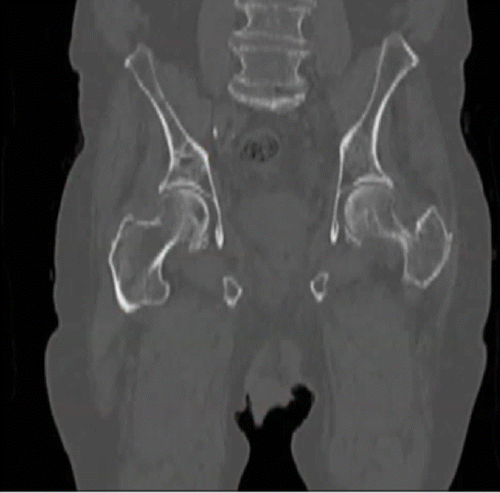

Gallium 68 (68Ga) PET targeting the prostate-specific membrane antigen (PSMA) enables detection of bone metastases not visible at bone scanning in a 100-year-old man with castration-resistant prostate cancer, a rising serum prostate-specific antigen (PSA) level (81 ng/mL), and a PSA doubling time of 2.7 months. Coronal unenhanced CT and 68Ga PSMA images show a false-negative result.